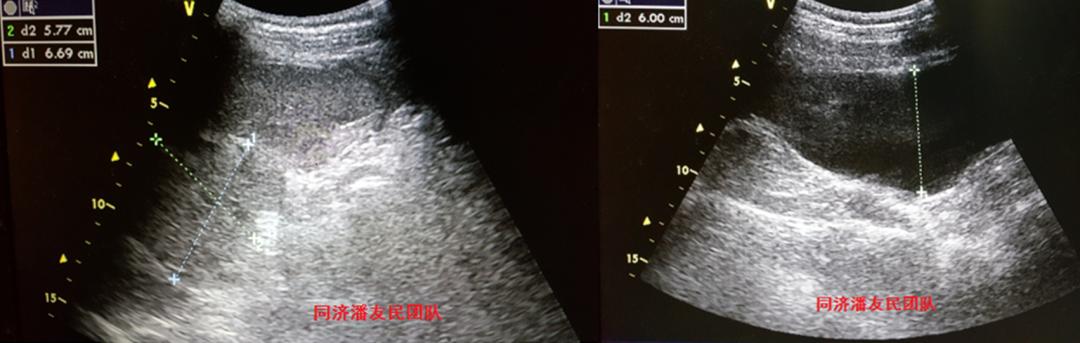

腹部彩超也证实脾破裂,腹腔积血(图4)。

心脏彩超、头部CT未见异常。初步诊断:车祸外伤、外伤性降主动脉夹层、脾破裂、失血性休克(早期)。